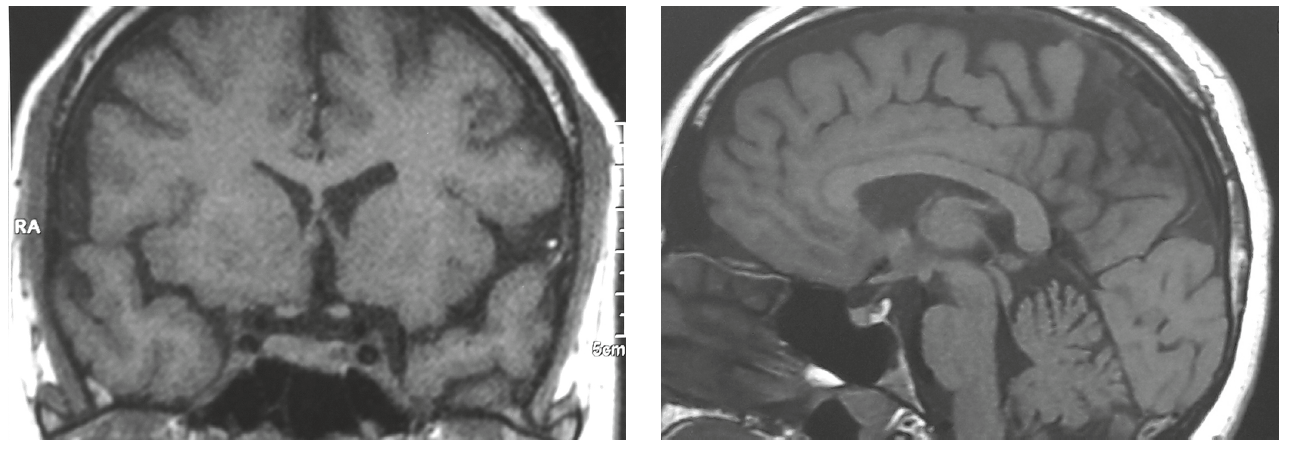

3. Fig. 2. MRI of the patient's R. brain with pituitary adenoma. | |